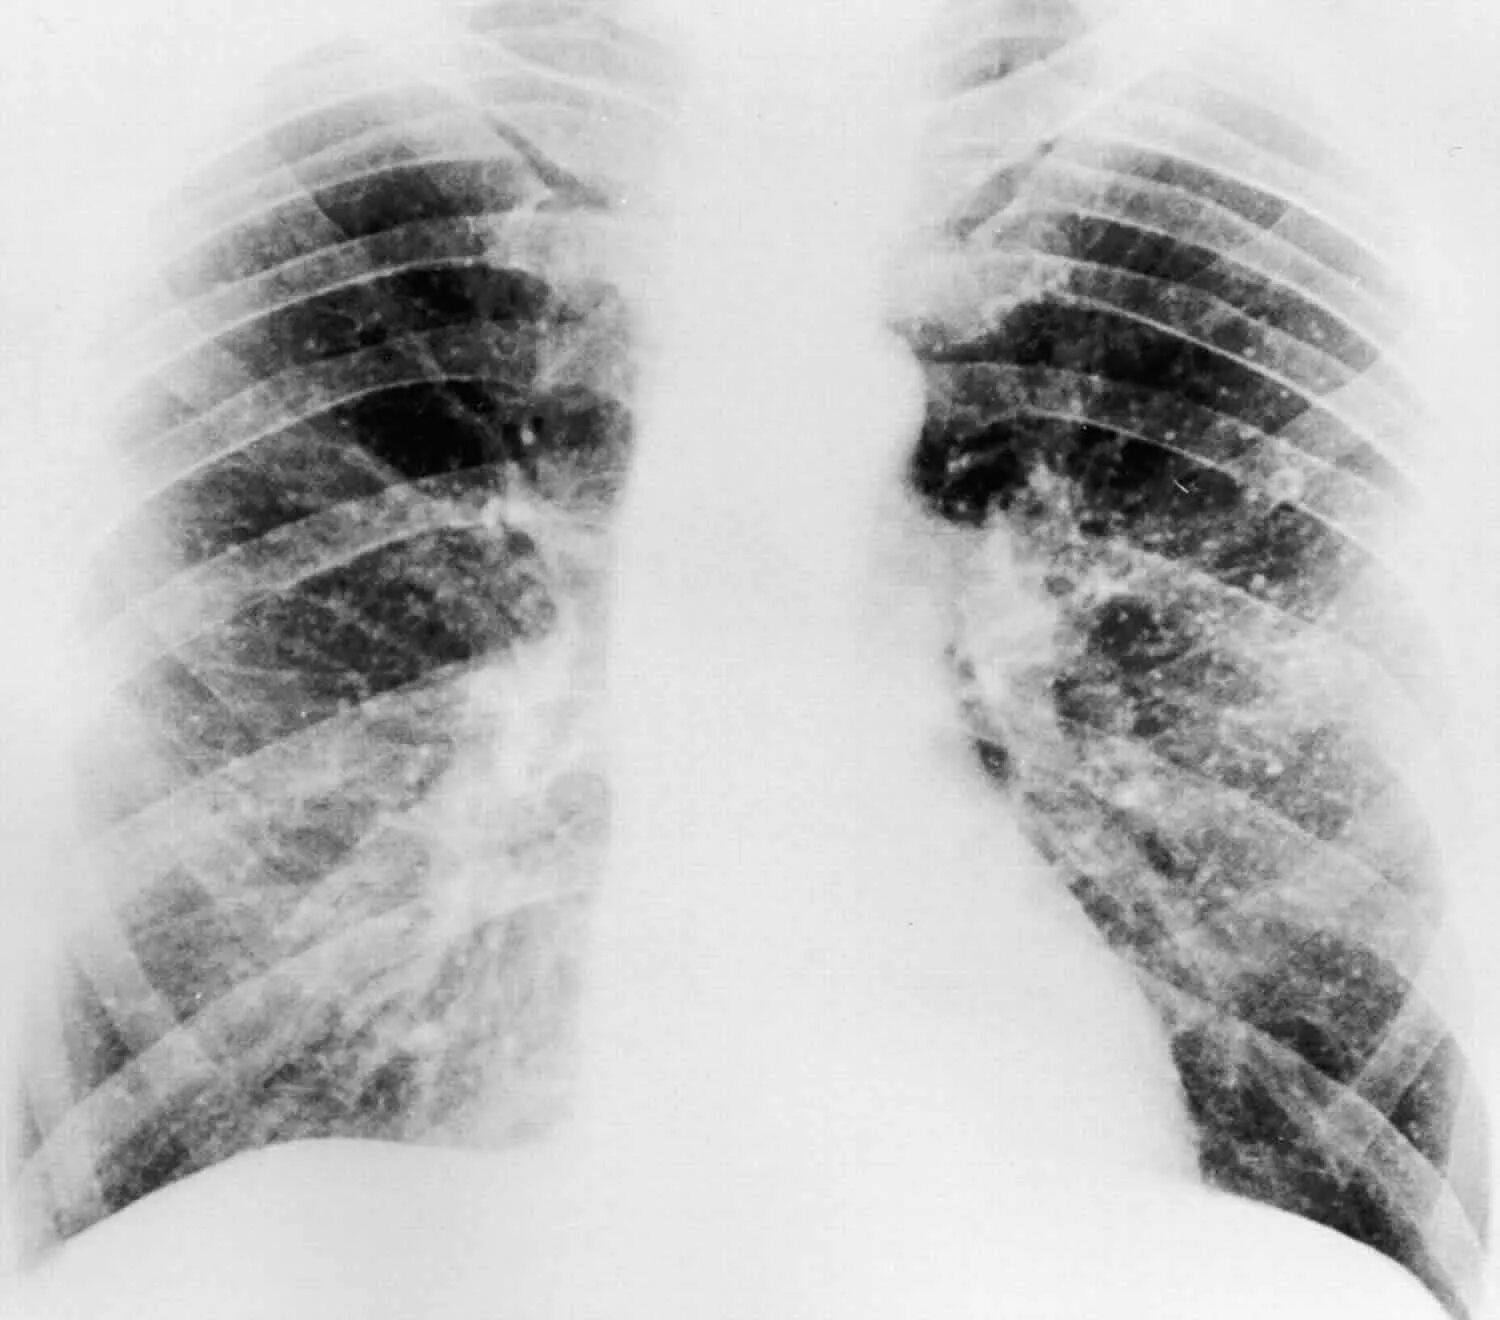

Гистоплазмоз это